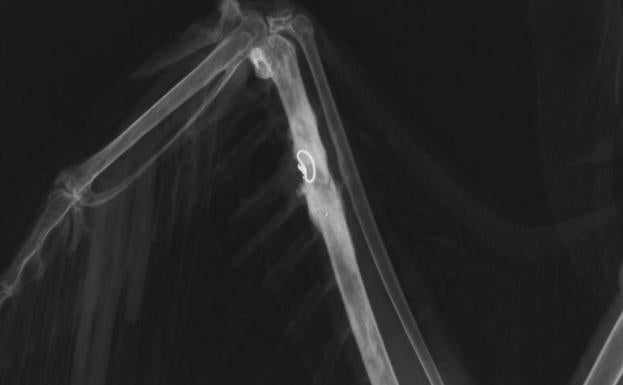

Imagen radiográfica postquirúrgica en la que se aprecia la consolidación ósea del implante.

Imagen radiográfica postquirúrgica en la que se aprecia la consolidación ósea del implante. (CEDIDA)